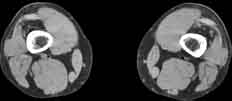

Visible Human male: Sectio transversalis 2242

CT

NMR

Pd                          / T2 \                         T1